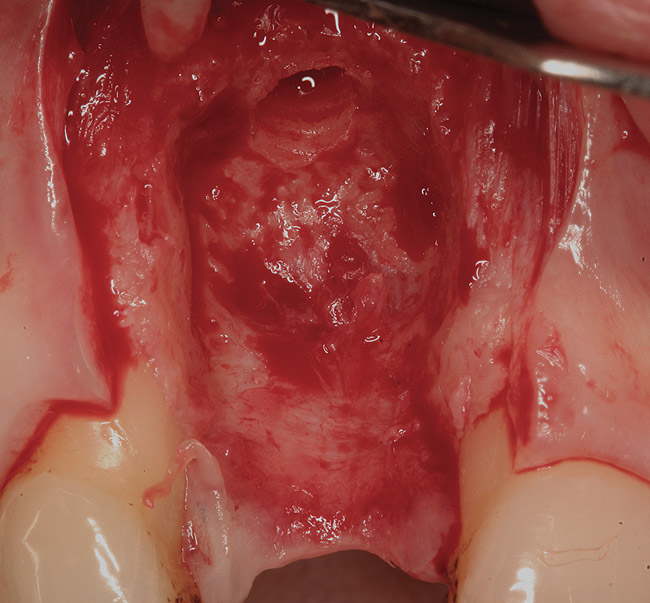

Figure 15  (Case 2) Defect after implant removal.

Figure 15

A 53-year-old woman presented with a failing implant in the No. 7 site (Figure 12 and Figure 13). Her desire was to eliminate infection and preserve esthetics. A team effort between the periodontist and restorative dentist to advocate for additional restorative dentistry as well as manage the patient’s expectation of time required was essential. In addition, the patient needed to have realistic expectations of a compromised outcome. Both the restorative dentist and the periodontist informed the patient about the difficulty of achieving this with acceptable esthetic results. Mutual emotional and technical support was required to successfully complete this case, from initial grafting of the defect to placement of anterior restorations (Figure 14 through Figure 23).